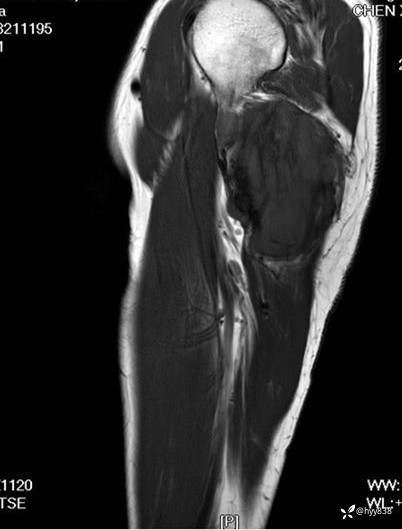

COR T2WI